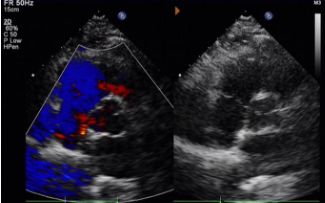

Dias 1 a 9 meses:

Nenhum desvio residual observado.

Redução gradual da ecogenicidade do dispositivo.